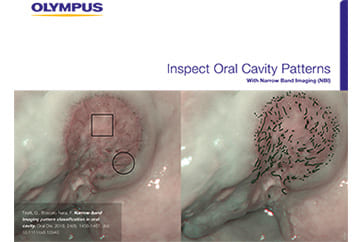

The lesion was detected in the oropharyngeal posterior wall in a laryngopharyngoscopic NBI examination during follow-up after treatment of a carcinoma in the floor of the mouth.

It was recognized under NBI as a lesion with a brownish area, and the close-up view additionally showed scattered brown dots. In the conventional white light image, the same area was seen as a reddening lesion.

The lesion was 5 x 3 mm and located on the back of the soft palate, and was diagnosed as a carcinoma in situ.